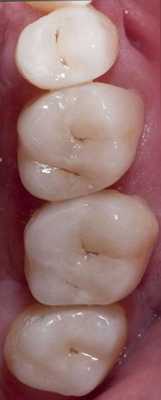

Фото 15-21. Последовательность клинических процедур: вид до вмешательства, вид прототипа, удаление прототипа, дефектных амальгамных пломб и остальных реставраций, нанесение кариес-маркера, запечатывание дентина и заполнение поднутрений, установка окончательных реставраций.

Фото 22-25. Фиксацию проводили из дистальных сегментов в направлении к фронтальным.

Фото 26. Вид после вмешательства.

Фото 27. Фронтальный вид после вмешательства.